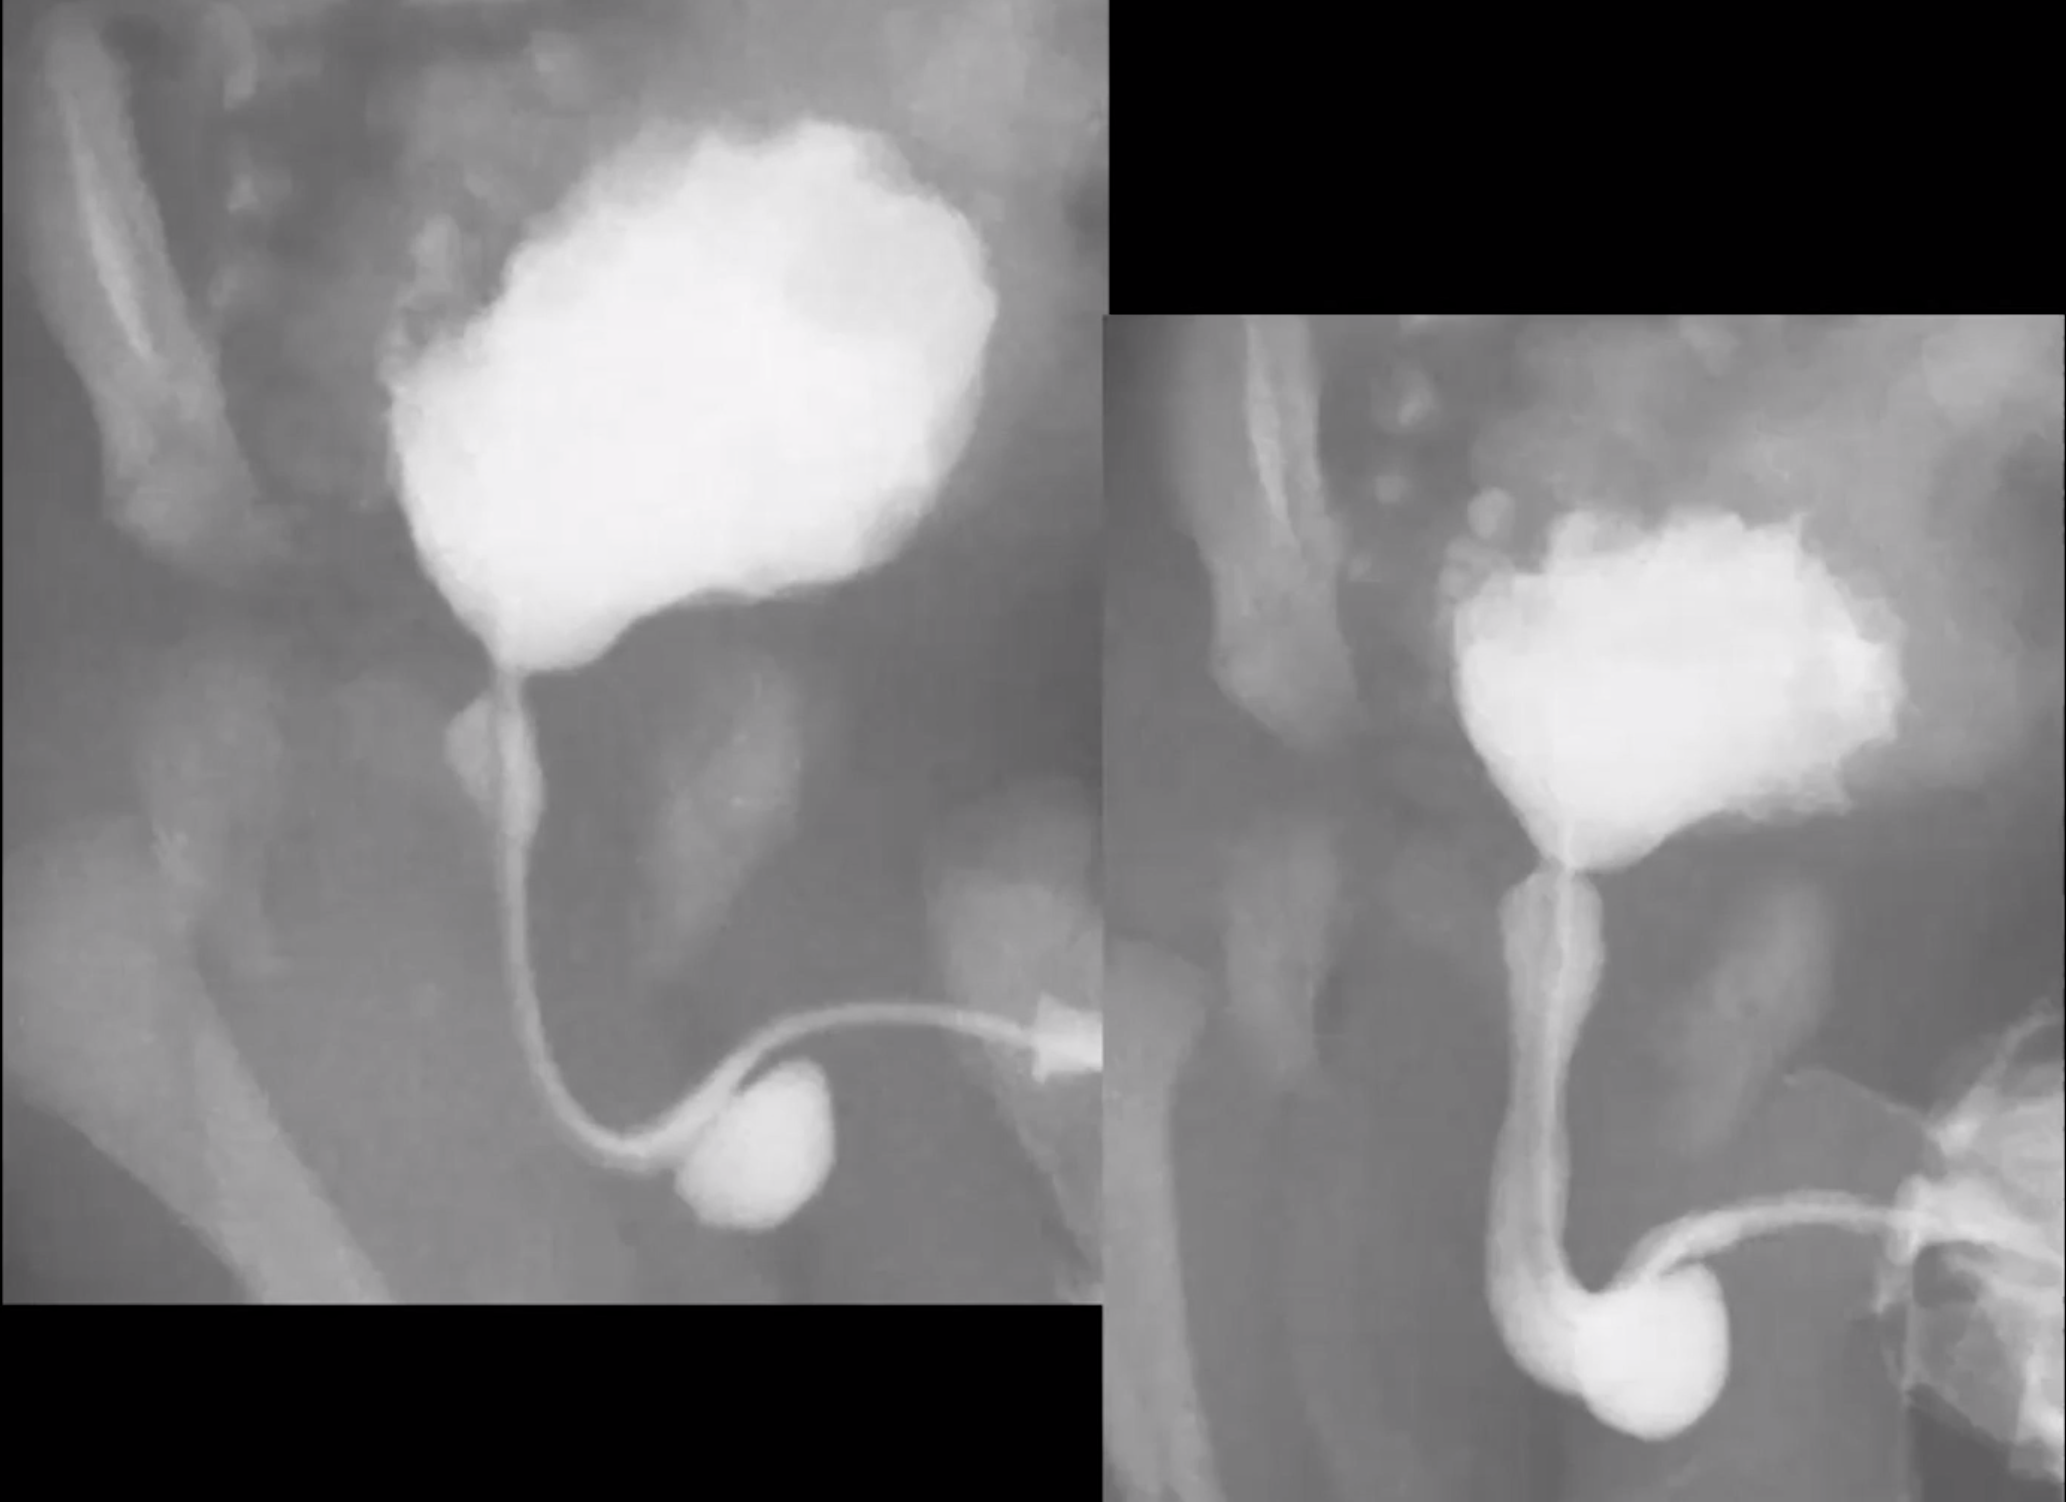

Posterior Urethral Valves

• Keyhole appearance

• Due to dilatation of the bladder and posterior urethra

• The bladder will typically have irregular contour due to chronic outlet obstruction - all because th ebladder is contracting against a closed door

• Elongated

• Trabeculated

• Maybe some diverticula

• Urinary ascites

• Severe unilateral vesicoureteral reflux

• Urinoma

• Large bladder diverticula

• These all basically act to relieve high pressure within the bladder

• Basically these are all protective features